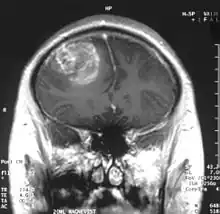

Le premier produit de contraste mis au point pour l'IRM est le gadolinium (Gd). En raison de sa toxicité, il faut l’emballer (le chélater) dans une molécule de DTPA. On a ainsi obtenu en 1984 le Gd-DTPA[81], qui avait le potentiel pour obtenir des IRM renforcés pour le diagnostic de lésions locales de la barrière hémato-encéphalique[82]. La molécule de Gd-DTPA est très polaire, et par conséquent bien trop hydrophile pour traverser une barrière hémato-encéphalique saine. Les modifications des jonctions serrées, comme celles qui peuvent par exemple être provoquées par un glioblastome, permettent le transport paracellulaire de ce produit de contraste dans le tissu cérébral. Là, il renforce le contraste, par interaction avec les protons de l'eau environnante, et rend visibles les défauts de la barrière hémato-encéphalique. Comme ce sont les vaisseaux responsables de l'alimentation de la tumeur qui sont touchés, dans son voisinage immédiat, on peut en apprécier l'extension.